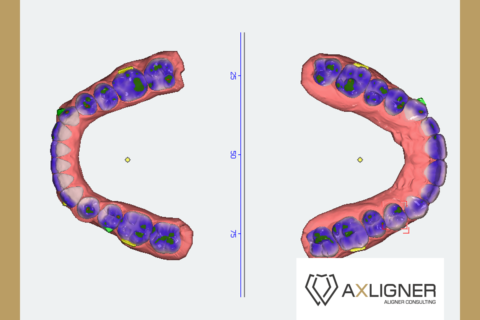

Analizę przemieszczeń zębów w zakresie mezjalizacji trzonowców w szczęce oraz przemieszczenie przedtrzonowca górnego rozpoczęto dopiero po uzupełnieniu zlecenia o analizę zdjęcia panoramicznego oraz badań dodatkowych. Opisano trzy opcje leczenia tego pacjenta. Pierwsza propozycja obejmowała brak mezjalizacji d. 26 i d.27; dystalizację w zakresie wybranych zębów. Druga propozycja obejmowała minimalną dystalizację drugiej ćwiartki łuku zębowego. Trzecia propozycja obejmowała sekwencyjną mezjalizację d. 26 oraz d. 27.

Cyfrowy plan leczenia przeanalizowano pod kątem osiągnięcia klinicznego celu zaplanowanego przez lekarza. Zaplanowana na cyfrowym planie leczenia mezjalizacja nie uwzględniała rekomendowanego sekwencyjnego przemieszczania zębów. Oznaczało to bardzo mało prawdopodobne zajście tych ruchów w jamie ustnej u pacjenta. Opisano lekarzowi, na czym polega sekwencyjna mezjalizacja zębów i jak zaprojektować ją w nowym planie leczenia. Zwrócono uwagę, że tego typu przemieszczenia zębów są bardzo wymagające, dlatego lekarze do zwiększenia możliwości ich zajścia stosują np. miniimplanty ortodontyczne. Opisano wpływ ilości i jakości attachmentów na zwiększenie przewidywalności ruchów zębowych.

- Zmodyfikować sekwencje mezjalizacji trzonowców.

- Plany leczenia dzielić na części, w których przemieszczane są pojedyncze zęby, a nie wszystkie zęby w maksymalnych zakresach jednocześnie.